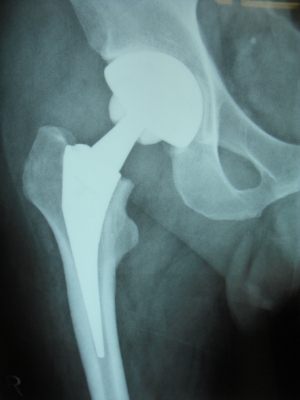

50歳 変形性股関節症 MIS-DAによる人工股関節置換術

術後3日目に歩行訓練開始し術後2週で杖なし歩行で退院

58歳 大腿骨頭壊死 MIS-DAによる右人工股関節置換術

術後2日で離床、3日めに歩行器歩行訓練開始、5日で杖歩行、7日で杖なし歩行可能となり2週で退院

86歳 続発性変形性股関節症 MIS-DAによる右人工股関節置換術

術後3週で杖歩行により退院